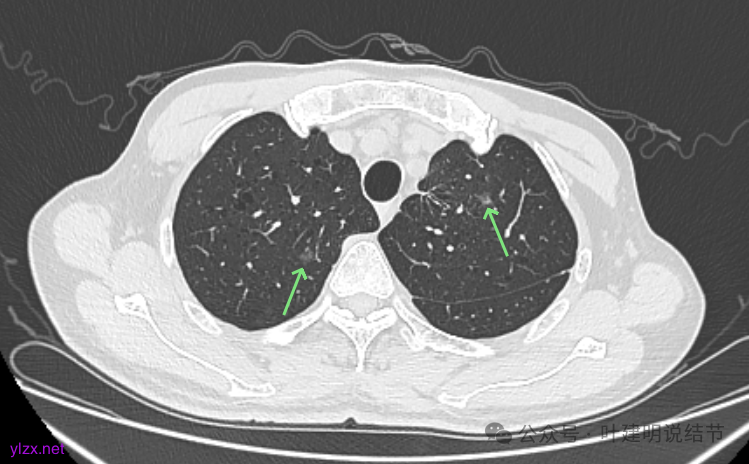

先看2020年9月的片子:

右上叶近脊柱旁有淡而纯的磨玻璃结节,整体轮廓与边界清楚,没有明显实性成分,也未见确切胸膜牵拉凹陷。

左上胸膜下有处偏长条小结节,也是磨玻璃密度的,轮廓较清。

左上叶前胸壁胸膜下有小结节,磨玻璃密度,有微小血管进入,轮廓与边界清。